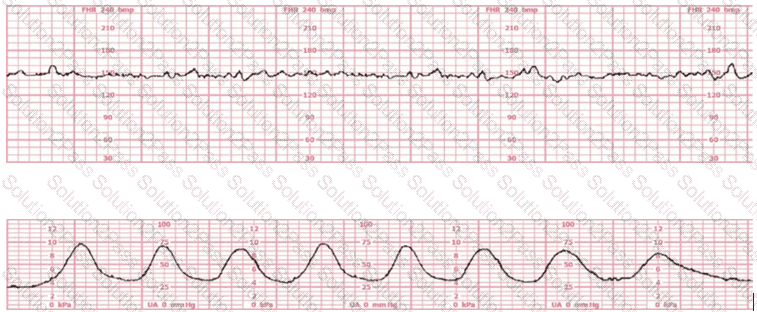

The pattern on the fetal heart rate tracing shown is likely due to

The fetal heart rate tracing shown demonstrates:

The tracing shown is a:

The most probable underlying fetal physiologic cause for this tracing would be:

The fetal heart rate tracing shown is obtained upon the woman's admission to labor and delivery. This tracing is most consistent with what maternal condition?

Prenatal diagnosis shows that a fetus has renal agenesis. During delivery, what type of electronic fetal heart rate pattern is most likely to be seen due to a common complication associated with this syndrome?